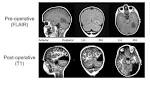

When surgeons removed one sixth of a child's brain, here's what happened

After losing chunk of brain, boy's visual system recovers

Brain's 'Plasticity' Amazes as Boy Recovers From Drastic Surgery